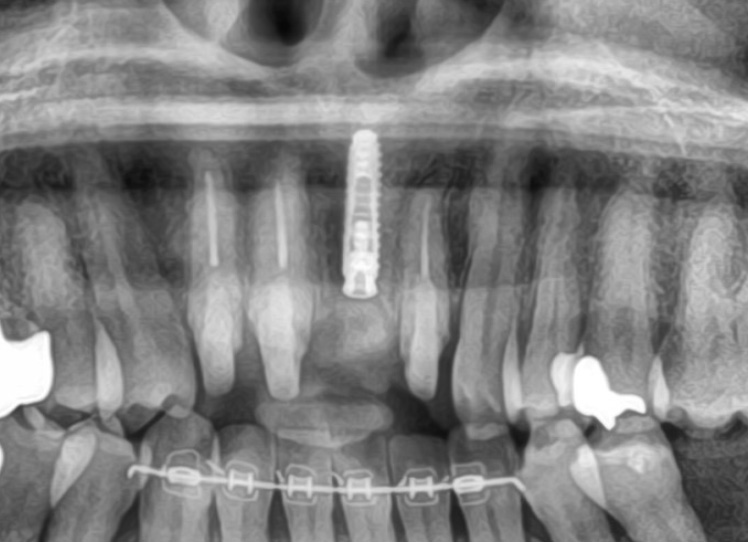

前歯が折れたため、インプラントにて治療。周りの歯の色調を合わせて自然な歯の入れを再現しました。

また、下の歯の歯並びも気にされていたので、ワイヤー矯正による部分矯正を行いました。

| 治療内容 | ・セラミックブリッジ、インプラント、ワイヤー矯正による部分矯正治療。 ・前歯が折れたため、インプラントにて治療。周りの歯の色調を合わせて自然な歯の入れを再現しました。 また、下の歯の歯並びも気にされていたので、ワイヤー矯正による部分矯正を行いました。 |